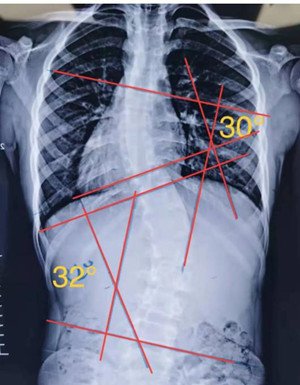

S型側(cè)彎,無論向哪個方向側(cè)躺,對其中一邊的彎度都是不利的,這種情況盡量以平躺為主。